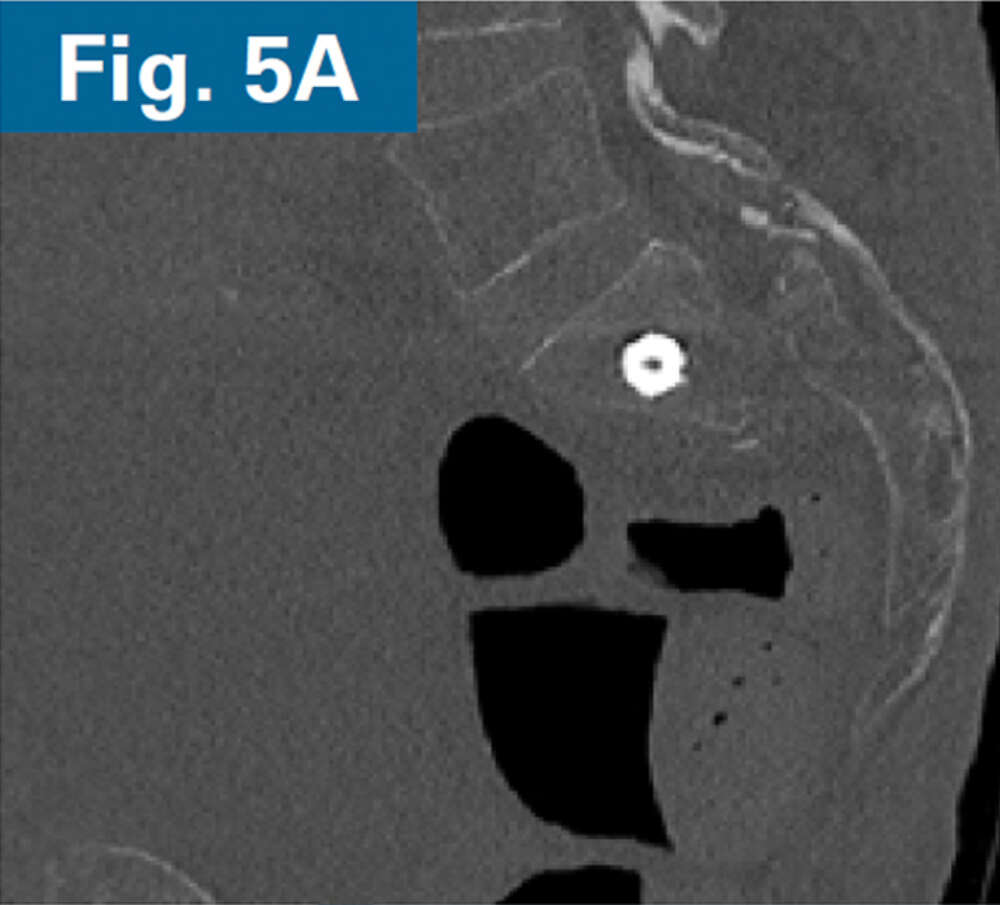

• 62 y/o male with COPD and 1 month old sacral U-type fracture after motorcycle crash (Figs. 1 and 2)

• Comminution and displacement of the right side component of his sacral U-type fracture significantly decreased the osseous corridor for placement of trans-sacral style screw in S1 requiring an iFuse TORQ® implant to provide sufficient fixation

• Immediate postoperative CT scan demonstrate safe placement of implants (Figs. 5A and 5B).